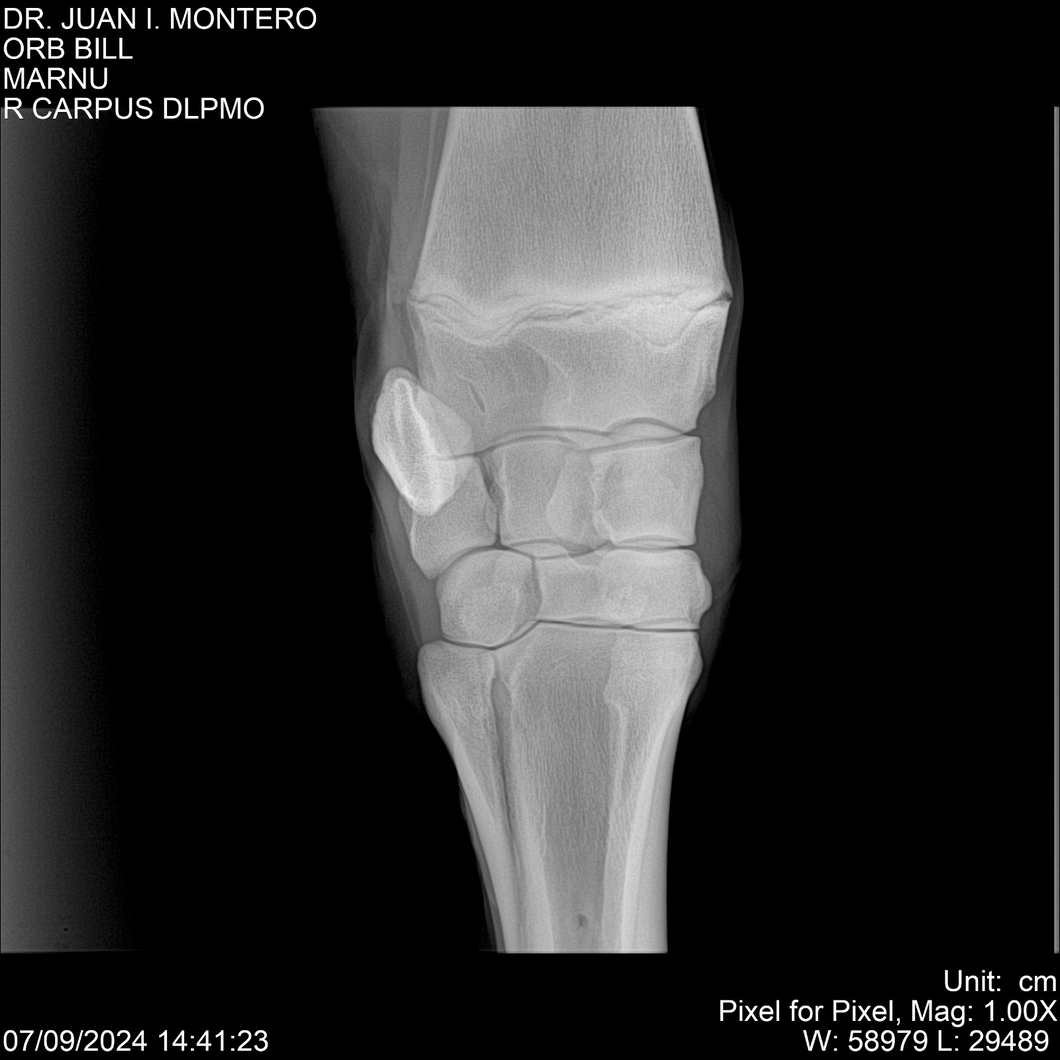

LOTE 7, ORB BILL 🔥 🔥 🔥 Lote Anterior Volver al remate Lote Siguiente Ficha Contacto Montevideo - Ficha del Lote Identificador: #282523 Categoría: Yeguarizos Montevideo - 83 Visualizaciones ClicData Contacto Empresa: Abelenda N. R., Walter Hugo Nombre*: Teléfono* : E-mail* : Mensaje Enviar Registrese gratis Este contenido Exclusivo está disponible sólo para usuarios registrados Ingresar